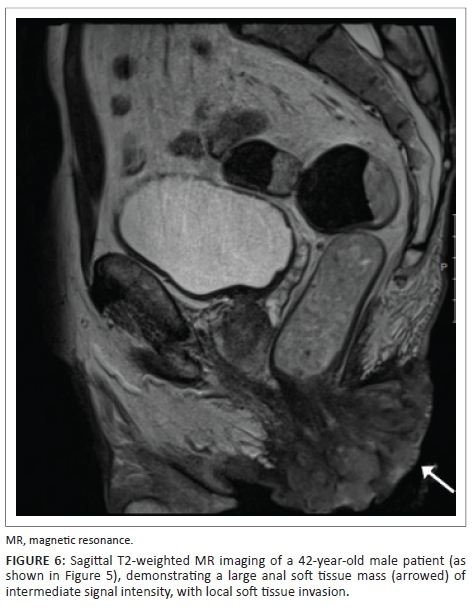

MRI is the preferred imaging modality for the assessment of anal tumours, providing detailed information regarding size, location and local invasion. The malignant tissue within the anal canal demonstrates low signal intensity on T1-weighted imaging. On T2-weighted imaging and short tau inversion recovery (STIR) sequences, it appears as intermediate signal intensity, lower than ischioanal fat.13

Figures 5 and 6 demonstrate a 42-year-old HIV-positive male patient, with a CD4 count of 16 cells/μL. T2-weighted imaging indicates a large, soft tissue mass, resulting in extensive soft tissue invasion. The mass demonstrates intermediate signal intensity, lower than the surrounding adipose tissue.